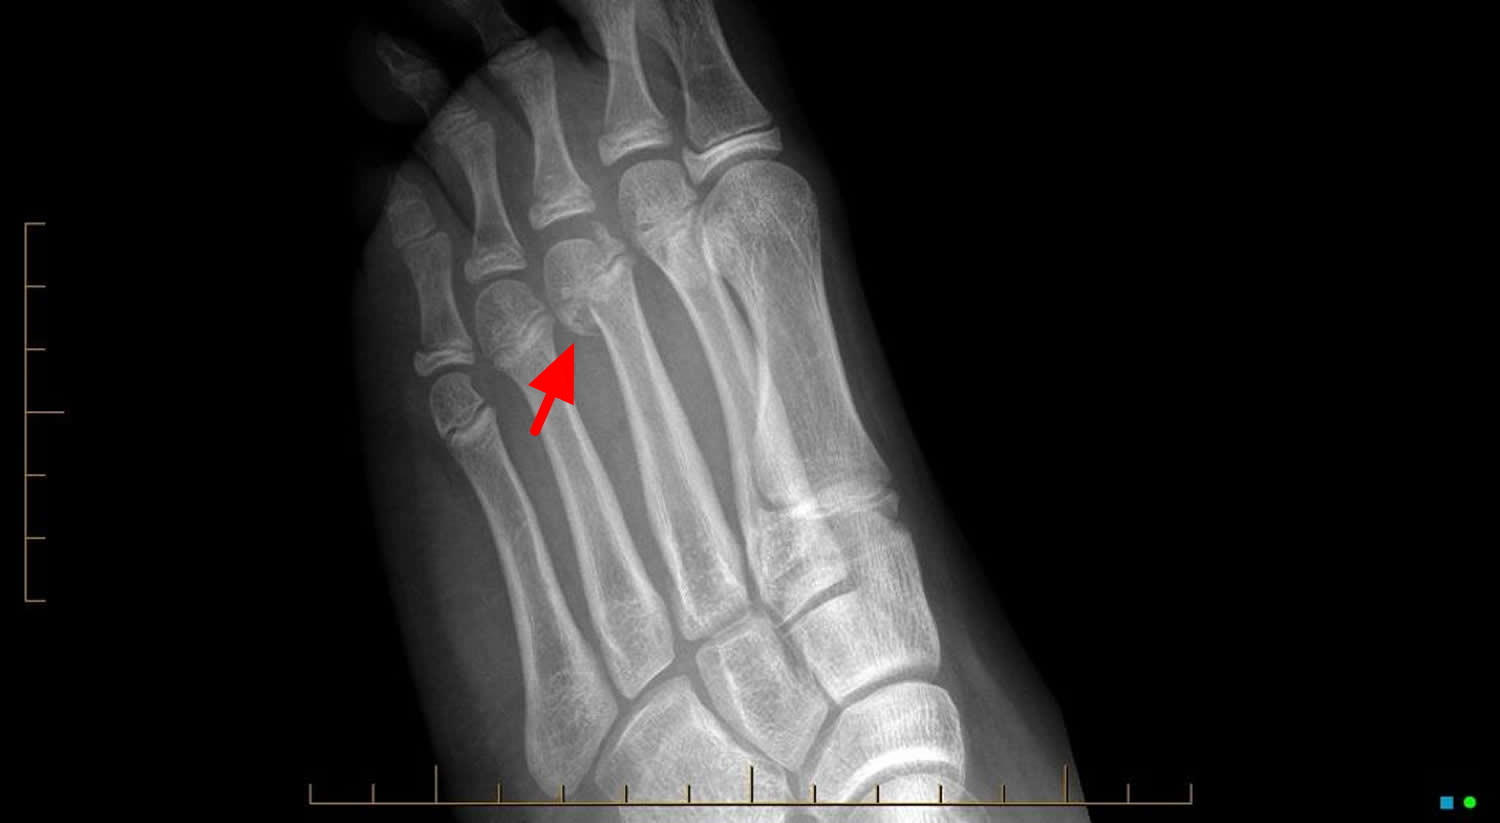

Growth Plate Injuries Require Prompt Treatment University of Utah Health

Growth Plate Fracture Causes, Types, Symptoms,Treatment How Many Growth Plates Do You Have In Your Body The growth plate, also known as the physis, is the cartilaginous. Understanding the function and importance of growth plates can provide insight into how the body grows and what happens when these. Myriad factors go into play when growing up. The bone grows in length and width at these areas. Time to read 5 min. A growth plate is an. How Many Growth Plates Do You Have In Your Body.

Growth Plate Fractures TeachMeSurgery How Many Growth Plates Do You Have In Your Body The bone grows in length and width at these areas. Most children grow an average of two years after they have completed their pubertal. Time to read 5 min. That is where new bone is added to increase the length of the long bone during development (called ossification). Myriad factors go into play when growing up. There is an average. How Many Growth Plates Do You Have In Your Body.